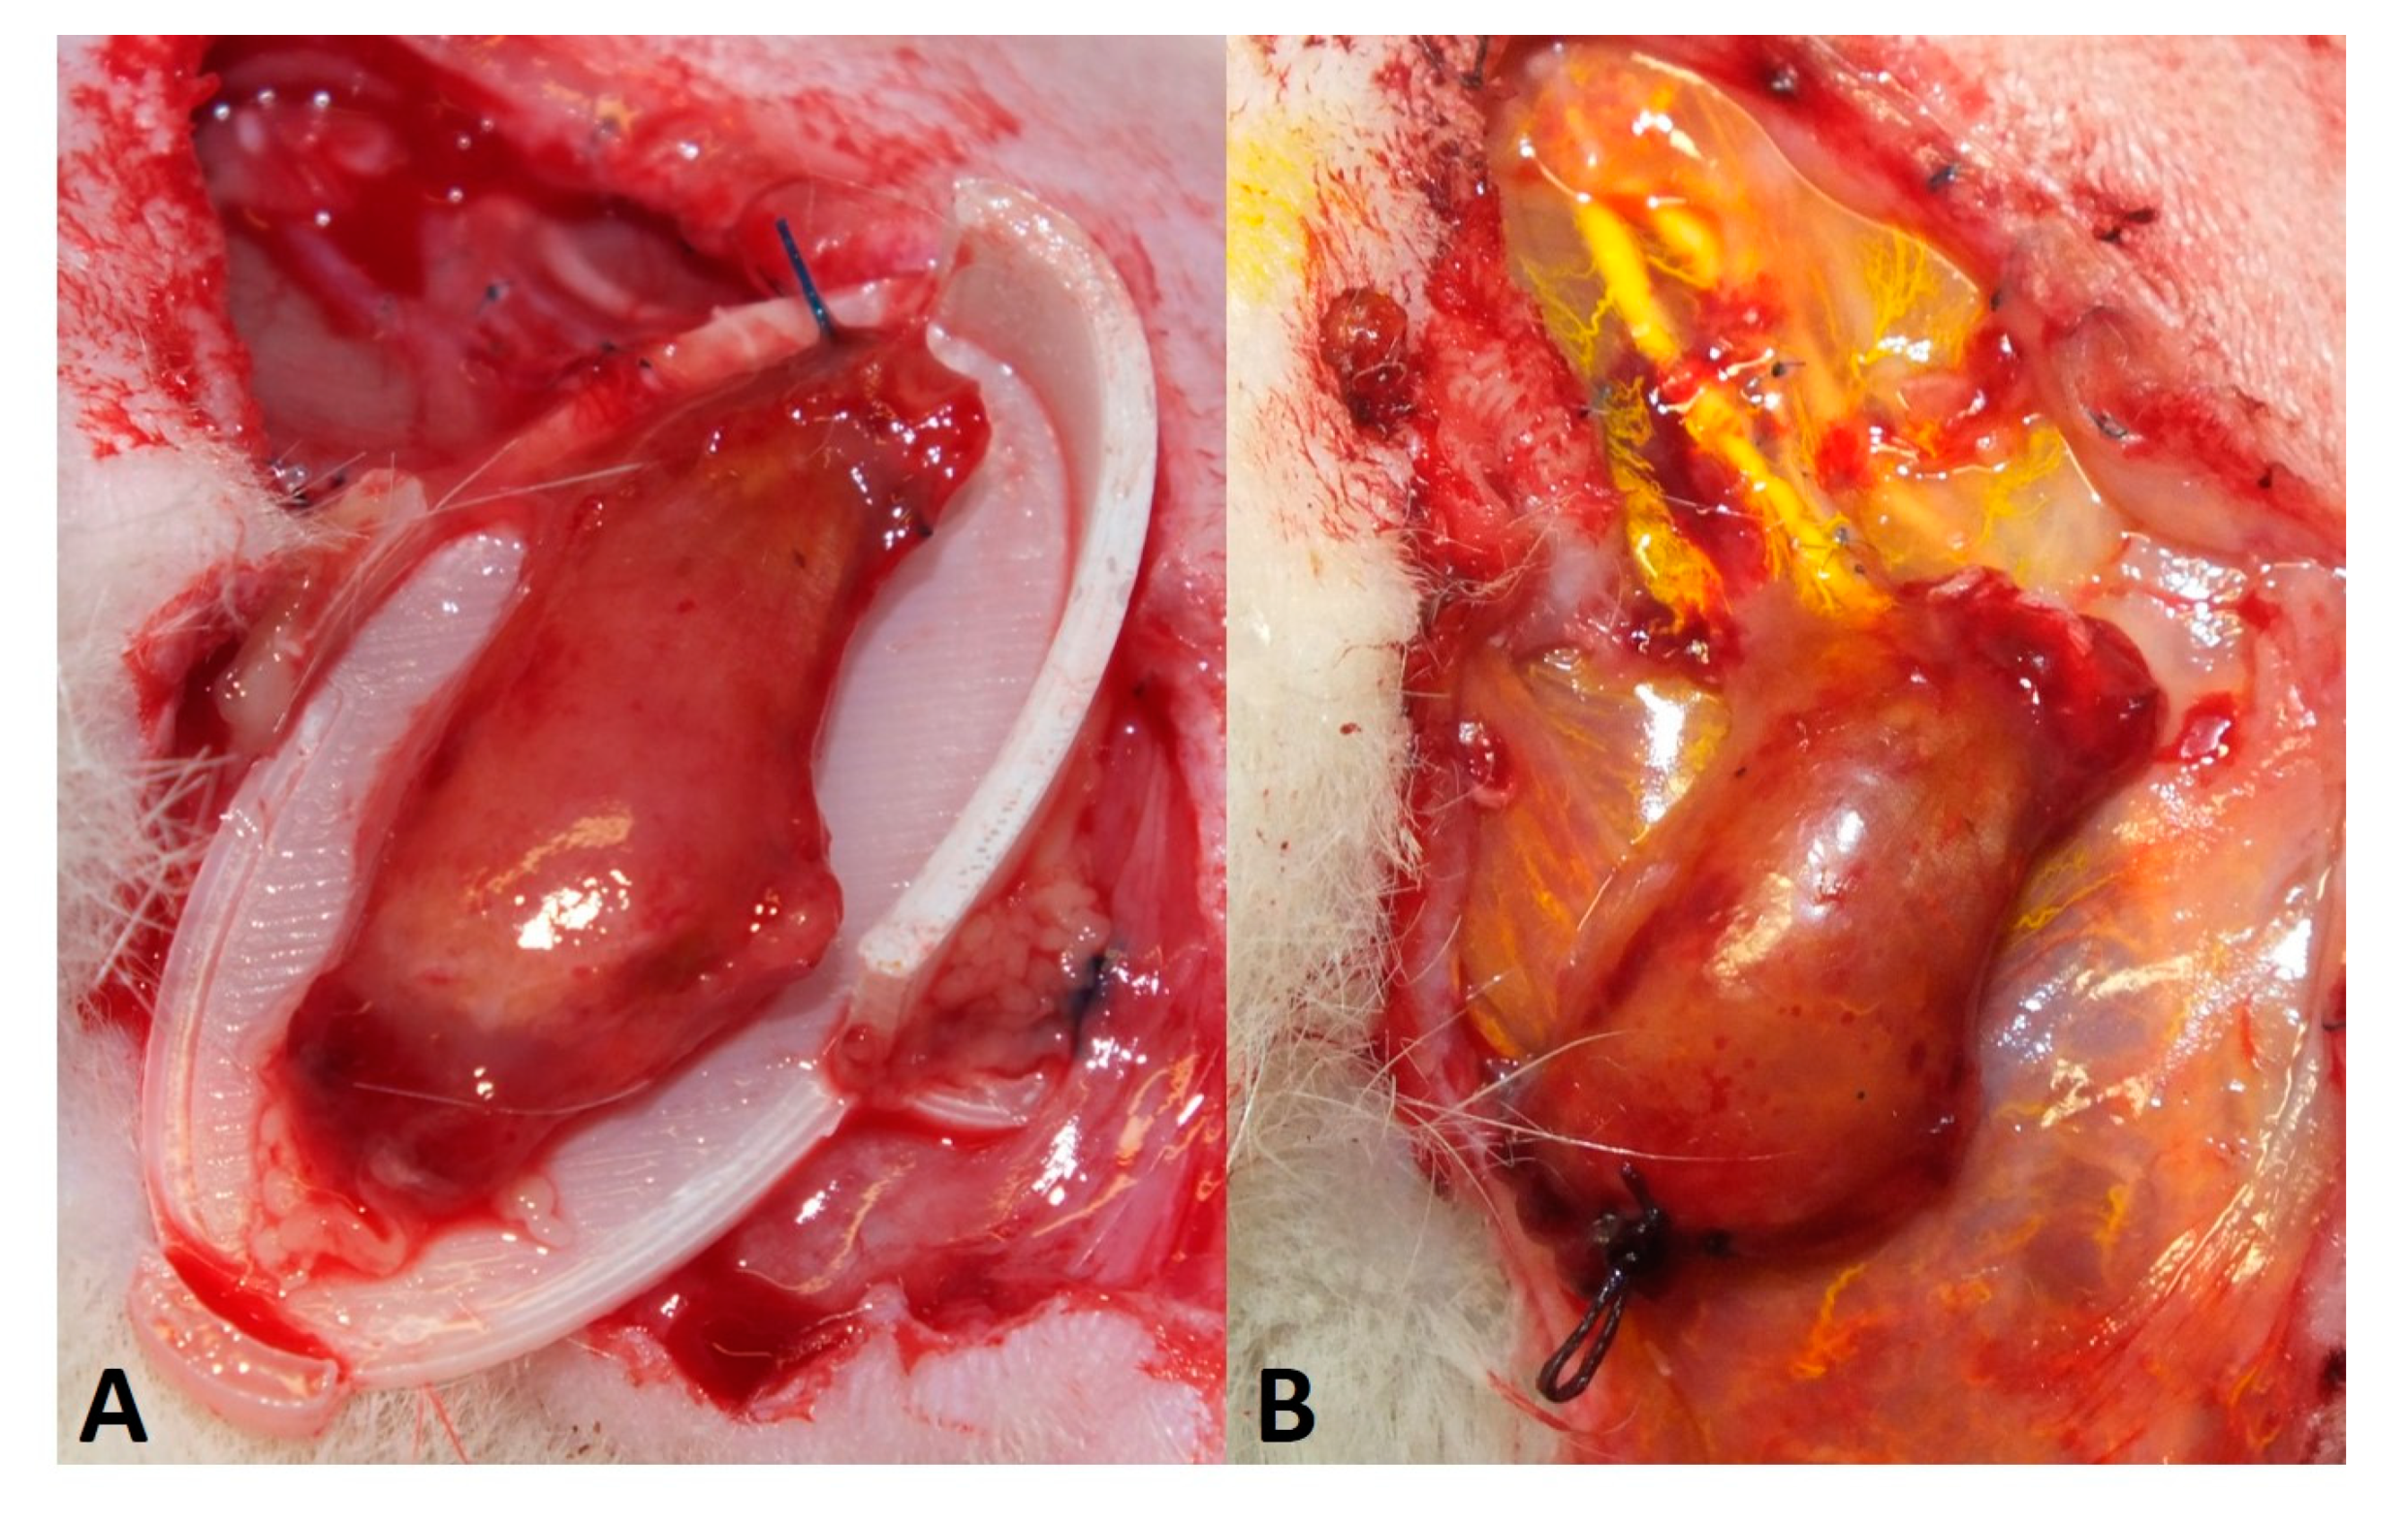

2.5. Perfusion and Explantation of Constructs

3.1. Surgery and Animals